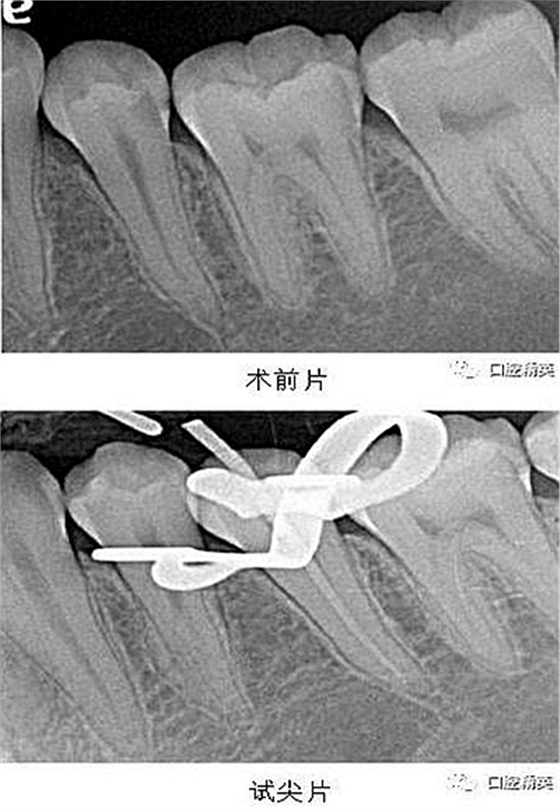

X-ray 可見:35 遠中齲壞累及髓腔,牙周膜增寬。

處置:經(jīng)患者及家屬知情同意后,35 局麻,放置橡皮障,去腐,開髓,可見黑色感染物流出,定位根管口,建立直線通路,10# K 銼疏通根管,確定工作長度(19mm),機用鎳鈦器械(M3),次氯酸鈉全程浸泡沖洗,預(yù)備根管至 35 號,0.04 錐度,2ml EDTA 沖洗液緩慢勻速沖洗,超聲蕩洗。試主尖 X-ray 可見恰充,吸潮紙尖拭干根管,導(dǎo)AH-Plus 糊劑,連續(xù)波熱牙膠垂直加壓充填,術(shù)后 X-ray可見根管恰充,SDR 封閉根管口,復(fù)合樹脂充填窩洞,恢復(fù)牙齒形態(tài),調(diào)牙合,拋光。醫(yī)囑